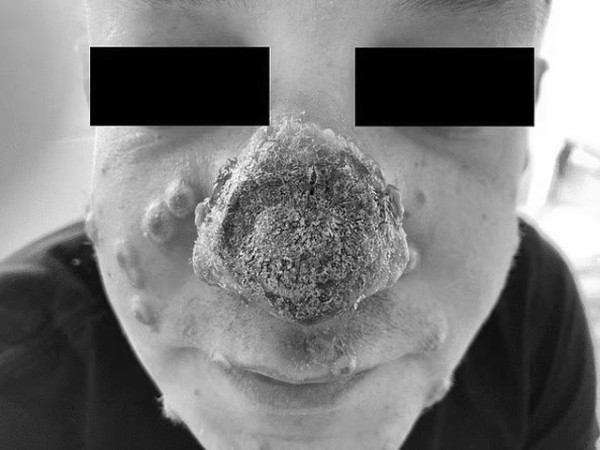

جرمنی میں منکی پاکس سے متاثر ایک شخص کی ناک گلنا شروع ہوگئی، حالیہ وباء میں ریکارڈ کیا جانے والا یہ معاملہ اپنی نوعیت کا سب سے تشویش ناک معاملہ ہے۔

میڈیا رپورٹس کے مطابق 40 سالہ مریض (جس کی شناخت ظاہر نہیں کی گئی) کچھ روز قبل اپنی ناک پر سرخ نشان کا معائنہ کرانے اپنے معالج کے پاس گیا تو اسے سن برن قرار دے کر واپس بھیج دیا گیا۔

تین دن میں مریض کی ناک کی جِلد مردار ہوکر سیاہ ہونی شروع ہوگئی، جس کے بعد ناک پر تکلیف دہ کھرنٹ جم گیا۔ اسی دوران متاثرہ شخص کے جسم پر پس سے بھرے دانے بھی نکل آئے۔

ایک پی سی آر ٹیسٹ کے بعد اس بات کی تصدیق ہوئی کہ وہ منکی پاکس سے متاثر ہے جس کے بعد اسے اسپتال لے جایا گیا اور اینٹی وائرل ادویات کی خوراک دی گئی۔ مزید معائنوں سے علم ہوا کہ مریض سائیفلِس اور ایچ آئی وی سے بھی متاثر تھا۔

مریض کو انفیکشن کے علاج کے لیے دوائیاں دی گئیں جس سے زخم تو سوکھ گئے لیکن ناک کی تکلیف میں جزوی طور پر بہتری آئی۔ متاثرہ شخص نے طبی ماہرین کو بتایا کہ اس سے قبل اس نے کبھی جنسی طور پر منتقل ہونے والے انفیکشنز کے متعلق ٹیسٹ نہیں کرایا تھا۔

ڈاکٹروں کا کہنا تھا کہ متاثرہ شخص کا معاملہ ایچ آئی وی کا علاج نہ کیے جانے کی وجہ سے انتہائی شدت اختیار کرچکا تھا جس کی وجہ سے ان کا مدافعتی نظام کمزور ہوچکا تھا جس کے سبب اسے نیکروسِس کا زیادہ خطرہ لاحق تھا۔

نیکروسِس ایک ایسی حالت ہوتی ہے جس میں ٹشو کسی انفیکشن کے سبب مردار ہونا شروع ہوجاتے ہیں۔